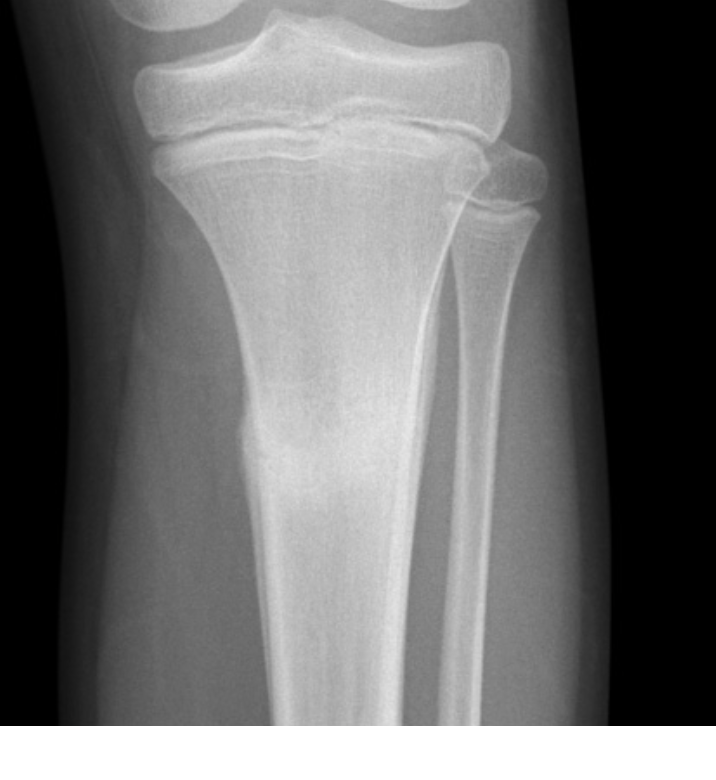

Describe the fracture seen in this X-ray [1]

Lateral tibial plateau fracture

* The fracture fragment is displaced and depressed from its normal position (dotted line)